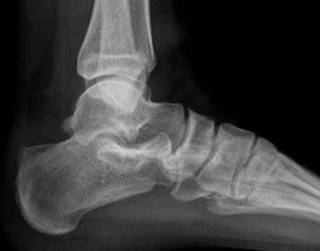

En nuestra primera consulta se envió a terapia física y rehabilitación realizando un total de ocho sesiones dentro de nuestra institución, no mostrando mejoría ni disminución del dolor, por lo que se solicitaron estudios de imagen, los cuales consistieron en radiografía anteroposterior y lateral de tobillo en la cual se evidenció adecuada congruencia de la articulación tibioastragalina y tibioperonea, exostosis posterosuperior de calcáneo de 6 milímetros de altura con relación a la línea articular superior, y alteraciones en la grasa de Kager (Figuras 1 y 2). De igual manera, se realizó resonancia magnética de tobillo evidenciando tendinitis aquílea, bursitis retrocalcánea y líquido en la bursa retroaquílea de aproximadamente 3 cm3. Se observa tendón aquíleo engrosado en su inserción y tendinitis insercional con edema óseo en región posterior de calcáneo (Figura 3).

Figura 1: Radiografía en proyección lateral de tobillo en la cual se evidencia exostosis en la parte superior del calcáneo, con alteraciones en la grasa de Kager.